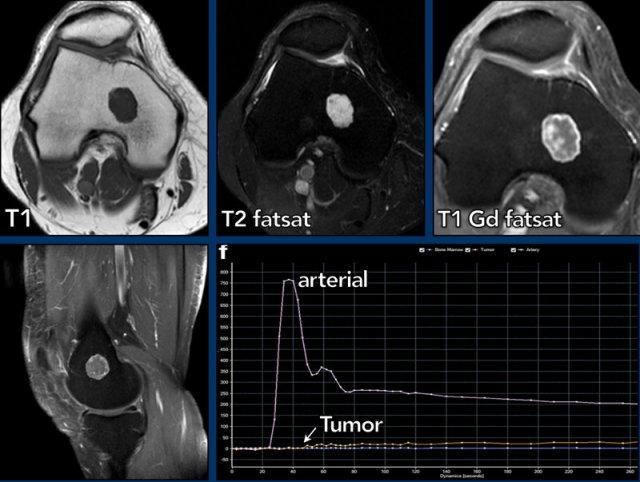

Tưới máu MR

Tưới máu hay MRI tương phản động là một kỹ thuật chẩn đoán hình ảnh chức năng trong đó sự ngấm thuốc sớm của khối u được theo dõi sau khi tiêm bolus gadolinium tĩnh mạch.

Trong các khối u sụn, tưới máu đã được sử dụng để phân biệt u sụn nội xương với u sụn ác tính.

Ngưỡng cắt 10 giây được sử dụng để phân biệt tăng ngấm thuốc nhanh và chậm. Tuy nhiên, có thể xảy ra sự chồng lấp trong các kiểu tăng ngấm thuốc sớm của các khối u sụn, ví dụ: u sụn lành tính (enchondroma) có thể tăng ngấm thuốc nhanh, nhưng cũng có các khối u sụn không điển hình (ACT) tăng ngấm thuốc chậm.

Hình ảnh

Có một khối u nhỏ hơn 2 cm ở hành xương đầu xa xương đùi.

Tổn thương tăng tín hiệu trên T2, đồng tín hiệu trên T1 và có ngấm thuốc dạng vách-nốt. Không có liên quan đến vỏ xương. Trên hình ảnh tưới máu (đường cong thời gian – cường độ tín hiệu), khối u cho thấy sự ngấm thuốc chậm, bắt đầu khoảng 20 giây sau khi động mạch ngấm thuốc.

Đây là u sụn trong xương và không cần theo dõi.

MR perfusion

ACT along the posterior cortex in the distal femur showing septonodular enhancement after contrast. Two ROIs were placed, one in the tumor (orange) and one in the popliteal artery (blue).

MRI tưới máu là một kỹ thuật chẩn đoán hình ảnh chức năng trong đó quá trình ngấm thuốc sớm của khối u được theo dõi sau khi tiêm bolus gadolinium tĩnh mạch.

Kỹ thuật này cung cấp thông tin về sự mạch hóa và tưới máu, tính thấm mao mạch và thể tích khoang kẽ.

Kỹ thuật này được sử dụng cho các khối u mô mềm và xương (chủ yếu tại các trung tâm ung thư chuyên biệt) trên toàn thế giới, và có thể hỗ trợ ví dụ như trong việc lựa chọn vùng không hoại tử để sinh thiết, hoặc để phân biệt tái phát tại chỗ với mô hạt. Tưới máu có thể giúp đặc trưng hóa các tổn thương và phân biệt tổn thương lành tính với ác tính.

MRI tưới máu thực chất có nghĩa là bạn đánh giá sự xuất hiện và thải trừ của thuốc tương phản gadolinium trong khối u theo thời gian.

Để thực hiện điều này, cần thu nhận các hình ảnh rất nhanh với độ phân giải thời gian cao (mỗi 2 hoặc 3 giây), trong khi thuốc tương phản đi vào và rời khỏi khối u trong tổng thời gian từ 3 đến 5 phút.

Sau khi thu nhận các hình ảnh động, giao thức thường được hoàn thành bằng các chuỗi xung tĩnh sau tiêm thuốc tương phản trên 2 mặt phẳng khác nhau.

Sử dụng phần mềm xử lý hậu kỳ, một vùng quan tâm (ROI) được vẽ trong một động mạch gần khối u. Tiếp theo, một hoặc nhiều ROI được vẽ trong khối u và trong một cơ lành để tham chiếu.

Các ROI khác nhau này sau đó được vẽ trên đường cong cường độ theo thời gian (TIC).

Trong các khối u sụn, tưới máu được sử dụng để phân biệt u sụn lành tính (enchondroma) với ung thư sụn (chondrosarcoma).

Ngưỡng cắt 10 giây được dùng để phân biệt ngấm thuốc nhanh và ngấm thuốc chậm. Tuy nhiên, có thể xảy ra sự chồng lấp trong các kiểu ngấm thuốc sớm giữa ung thư sụn (CS) và u sụn lành tính, ví dụ: một số u sụn lành tính có thể ngấm thuốc nhanh, nhưng cũng có những khối u sụn ác tính độ thấp (ACT) ngấm thuốc chậm.

Ví dụ về một ACT tăng cường chậm (đường màu cam), hơn 10 giây sau động mạch (đường màu xanh lam).